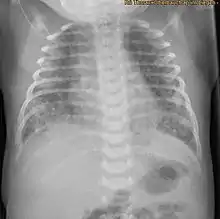

X-ray showing the extent of lung epithelial damage in response to meconium seen in neonates with meconium aspiration syndrome.

Respiratory distress in an infant born through the darkly coloured MSAF as well as meconium obstructing the airways is usually sufficient enough to diagnose MAS. Additionally, newborns with MAS can have other types of respiratory distress such as tachypnea and hypercapnia. Sometimes it is hard to diagnose MAS as it can be confused with other diseases that also cause respiratory distress, such as pneumonia. Additionally, X-rays and lung ultrasounds can be quick, easy and cheap imaging techniques to diagnose lung diseases like MAS.[16]